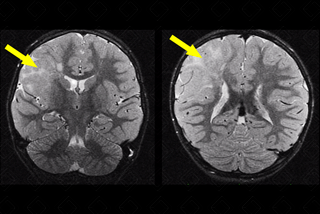

Texto alternativo para a imagem Figura 3. Créditos: Dra. Elazir Mota - Rio de Janeiro/RJ

Descrição da figura 3: Ressonância magnética plano coronal e axial T2 revelando imagem hiperintensa, expandindo sulcos e giros nos lobos parietal e frontal direitos (setas amarelas). [cms-watermark]

• Túberes corticais: Essas lesões expansivas do SNC isoladamente não são diagnósticas de esclerose tuberosa, podendo ser observadas em outras patologias. Trata-se de hamartoma benigno presente no córtex de cerca de 95% dos pacientes com esclerose tuberosa. Esse tipo de alteração relaciona-se diretamente com as alterações e o quadro neurológico observado nesses doentes, incluindo epilepsia, distúrbios cognitivos e de comportamento. Caracterizam-se na ressonância magnética como lesões bem circunscritas, de baixo sinal em T1 e alto sinal em T2. Na maioria dos casos, a tomografia computadorizada do crânio falha na detecção dessas lesões ( figuras 3 e 4) ;